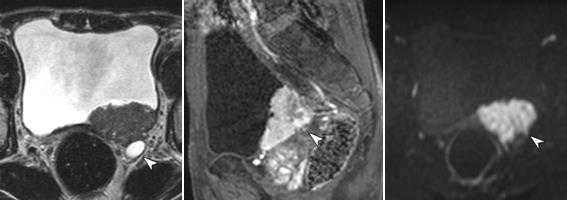

Инфильтративно растущие опухоли мочевого пузыря.

а) Т2 cor FS б) Т2-tra

Женщина, 56 лет. Клинически - гематурия, морфологически верифицированная опухоль мочевого пузыря. На представленных бесконтрастных Т2-взвешенных изображениях в корональной (а) и аксиальной (б) плоскостях видно асимметричное инфильтративное утолщение левой стеки мочевого пузыря, ригидность и уплощение левой стенки на фоне нормального наполнения пузыря. При этом наружный контур инфильтративно утолщенной стенки имеет нечеткие контуры.

Внутривенное динамическое контрастирование, Т1-ВИ, ранняя (артериальная фаза). Видно выраженное диффузное контрастное усиление всей толщины инфильративно измененной левой (и частично задней) стенок мочевого пузыря, с нечеткостью ее наружного контура и признаками минимального экстравезикального распространения.

Метастазы рака мочевого пузыря

Аксиальное Т1-взвешенное изображение (а), Т2-ВИ с жироподавлением (б) у пациента с раком мочевого пузыря. Определяется мелкое объемное образование шейки левой бедренной кости (стрелки). При внутривенном контрастном усилении (с) - Т1 c FS определяется усиление данного мелкого образования, что позволяет подтвердить вторичную, метастатическую природу данного очага, несмотря на его малые размеры.